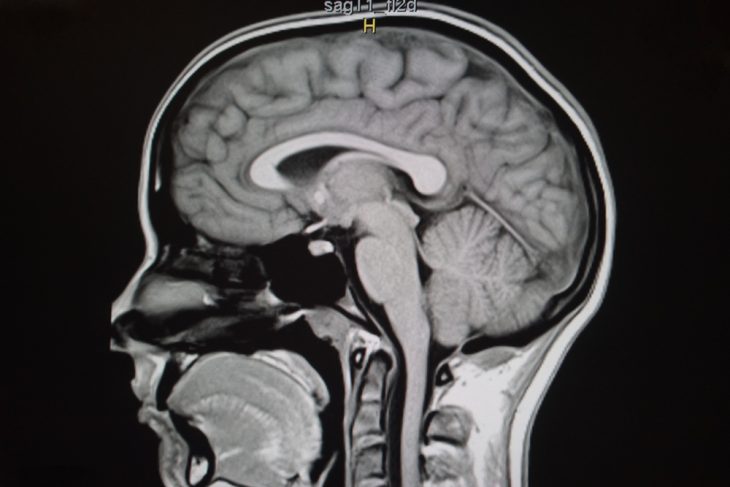

Магнитно-резонансная томография (МРТ) – это высокоинформативный метод лучевой диагностики, который позволяет обнаружить даже минимальные изменения в тканях гипоталамо-гипофизарной системы и точно указать, где именно они локализованы. Исследование не требует какой-либо серьезной подготовки к нему и, как правило, хорошо переносится больными.

Гипофиз – это придаток головного мозга, имеющий округлую форму и расположенный в костном кармане – турецком седле. Это центральный орган эндокринной системы, в нем вырабатываются гормоны, регулирующие работу всего организма. Размеры его весьма индивидуальны, но в любом случае можно говорить о том, что данная железа невелика (в длину она достигает 5-13 мм, в ширину – 3-5 мм, а высота ее – 6-8 мм).

Не любая диагностическая манипуляция справится с такой задачей, ведь чтобы оценить изменения в отдельных частях гипофиза, необходимо получить его изображения максимально возможного разрешения и как можно меньшей толщины. В идеале толщина среза должна составлять лишь 2-3 мм.

Некоторые магнитно-резонансные томографы вполне могут обеспечить высокое напряжение магнитного поля, обеспечивающее идеальное качество снимков при минимальной толщине среза. Другие методы диагностики (рентгенография, компьютерная томография) конкурировать с МРТ в этом отношении не способны.

К тому же, МРТ предоставляет изображение исключительно структур гипофиза и тканей, его окружающих, а при проведении некоторых других исследований на эти структуры наслаивается костная ткань или другие, затрудняющие диагностику образования – это снижает информативность исследования.

Отдельно хотим отметить, что МРТ головного мозга и МРТ гипофиза – не одно и то же исследование. Поскольку последнее требует прицельной диагностики конкретной области мозга, проводить его в составе другого исследования нецелесообразно, информация, полученная при этом, будет неполной. Если имеется подозрение на то, что патологический процесс локализован именно в области гипофиза-гипоталамуса, необходимый метод диагностики в такой ситуации – только МРТ гипофиза.

Компьютер при помощи ранее установленной специальной программы обрабатывает полученные с томографа сигналы и генерирует из них определенное количество изображений (согласно числу срезов). Они могут иметь различную толщину и быть получены под разными углами (характером срезов руководит врач-рентгенолог во время проведения МРТ). Когда изображения сформированы, врач оценивает патологические изменения на них непосредственно с монитора, а также распечатывает фото и/или записывает их на диск, после чего передает пациенту или его лечащему врачу.

В норме на срезе, сделанном во фронтальной плоскости (будто бы аппарат «смотрит» пациенту прямо в лицо), форма гипофиза напоминает прямоугольник. Нижний его контур имеет форму турецкого седла, а верхний – вогнутый, горизонтальный или выпуклый. Передне-задний и право-левый размеры органа соответствуют таковым собственно турецкого седла, а вертикальный варьируется в пределах 4-8 см и изменяется при заболеваниях. У подростков вертикальный размер может превышать вышеуказанные значения – возрастать до 9-10 мм, а у женщин в конце беременности и в послеродовом периоде – увеличиваться до 10-12 мм.

На фронтальном срезе гипофиз в основном симметричен (легкая асимметрия является скорее вариантом нормы, нежели признаком патологии). Воронка органа располагается по срединной линии, однако небольшое отклонение от нее при отсутствии структурных изменений гипофиза и других патологических изменений в области железы специалисты также расценивают как норму.